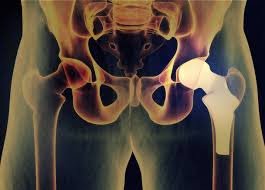

Joint replacement surgery, also known as arthroplasty, has a history dating back to the early 20th century when the first documented hip replacement was performed. Since then, this field has seen remarkable progress in materials, surgical techniques, and patient outcomes.

One of the key advancements in joint replacement surgery is the development of improved materials for prosthetic joints. In the past, joint replacements were made primarily of metal and plastic components. Today, advancements in biomaterials have led to the creation of highly durable and biocompatible materials like ceramic and metal alloys. These materials mimic the natural joint’s structure and function, providing a more natural range of motion.

Every patient’s anatomy is unique, and the development of customized implants has allowed for a more personalized approach to joint replacement surgery. Using advanced imaging and 3D printing technology, surgeons can create implants that match the patient’s specific joint dimensions, leading to a better fit and improved functionality.